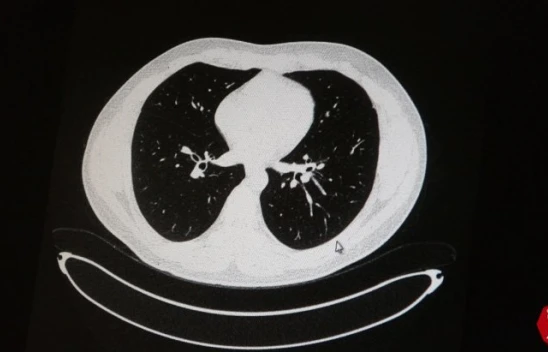

Fırat Üniversitesi (FÜ) Bilgisayar ve Öğretim Teknolojileri Bölümü Öğretim Üyesi Doç. Dr. Zülfü Genç öncülüğünde, Türkiye'de ilk defa yapay zeka tabanlı 'ses ve öksürük' ile korona virüs başta olmak üzere bir çok hastalığın teşhisi ile ilgili yazılım geliştirildi.

3 bin veri ile ses ve öksürük kayıtlarına göre kişinin korona virüs olup olmadığını saptadıklarını belirten Doç. Dr. Genç, başarı oranının ise yüzde 60 ila 80 arasında olduğunu kaydetti.

Gelişen teknolojiyi takip eden ve daha önceden birçok proje ile ilklere imza atan Fırat Üniversitesi, her alanda ülkenin gelişmesine katkı sağlamaya devam ediyor. Son olarak Bilgisayar ve Öğretim Teknolojileri Bölümü Öğretim Üyesi Doç. Dr. Zülfü Genç ve ekibi tarafından giyilebilir sensörler ve yapay zeka destekli bir yazılım ve uygulaması olan “Hastalık Teşhisi ve Hasta Takibi için Yapay Zeka Destekli Akıllı Bileklik Tasarım ve Uygulaması” Projesi KOSGEB ve ilgili kurullar tarafından kabul edilerek desteklendi. Proje ile belirli semptomları gösteren hastaların, giyilebilir sensörlerden alınan sinyalleri yapay zeka destekli yazılım ile işleyerek doktorların kullanabileceği karar destek sistemi oluşturma amacında olduklarını ifade eden Doç. Dr. Genç, yaygın semptomları ateş ve öksürük şeklinde olan korona virüs enfeksiyonunun verilerini bu yazılım ile işleyerek erken teşhis ve kesin tanıdan sonra hastanın uzaktan canlı takip sistemini proje kapsamında başarı ile gerçekleştirdiklerini belirtti. Yazılımda öksürük sesinden hızlı korona virüs testi çalışmalarının devam ettiğini dile getiren Doç. Dr. Genç, ilk kez bu testin mobil uygulamaya eklendiğini ve yüzde 60 ila 80 arasında doğru sonuç alındığını vurguladı. Doç. Dr. Genç, projenin sağlık çalışanı ve hasta arasında güvenli bir veri iletişimi ve etkin takip sayesinde sağlıkta yerli, milli çözüm ile konfora ulaşılmasının yanı sıra bu entegrasyon sayesinde telefonda hızlı bir şekilde korona virüs testi alma olanağını ortaya çıkaracağını bildirdi.

Yazılımdaki en önemli özelliğin ses ve öksürükle kişinin korona virüse yakalanıp yakalanmadığını büyük oranda tespit edebildiği olduğunu vurgulayan Doç. Dr. Genç, “Yazılımda geldiğimiz en önemli noktalardan biri de korona virüs teşhisinin öksürükle tespitini gerçekleştiren yazılım üzerinde çalışmalarımız devam etmektedir. Elimizdeki yaklaşık 3 bin tane veri ile herhangi bir kişiden almış olduğumuz ses ve öksürük kayıtlarına göre kişinin korona virüs olup olmadığına karar vermeye çalışıyoruz. Bizim devam ettirdiğimiz çalışmalarda yüzde 60 ila 80 arasında bir başarı elde ederek bir kişinin öksürük ve ses verisinden korona virüs olup olmadığını da saniyeler içerisinde tespit edebiliyoruz. Bunun Türkiye’de ilk olduğunu düşünüyoruz. Dünyada çok değişik çalışmalar yapıldığını biliyoruz, onları da yakından takip ediyoruz. Şuan halihazırla Diyarbakır ve Mardin’de hastalarımızın üzerinde de bu saatler var ve onlar üzerinden veriler alıp onların anlık takiplerini gerçekleştirebiliyoruz. Bu yazılım sistemi sayesinde hastanın anlık verilerini doktoru ve onun bağlı olduğu tüm sağlık birimlerindeki kişiler hatta Sağlık Bakanı da bu verileri görebilme şansına sahip olabilecek. Bu yazılımla ilgili çalışmalarımız devam ediyor. Üretim anlamında bir yatırım desteği söz konusu olması gerekiyor. Projemizle ilgilenen hem özel hem de devlet kuruluşları yaptığımız çalışmaları yakından takip ediyor. İlk etapta bine yakında saati üretip hastalarımıza vererek yazılım sistemimizi güçlendirmeyi düşünüyoruz. Geliştirmiş olduğumuz proje sayesinde sağlık çalışanı ve hasta arasında güvenli bir veri iletişimi ve etkin takip sayesinde sağlıkta yerli, milli çözüm ile konfora ulaşılmasını sağlıyoruz” şeklinde konuştu.